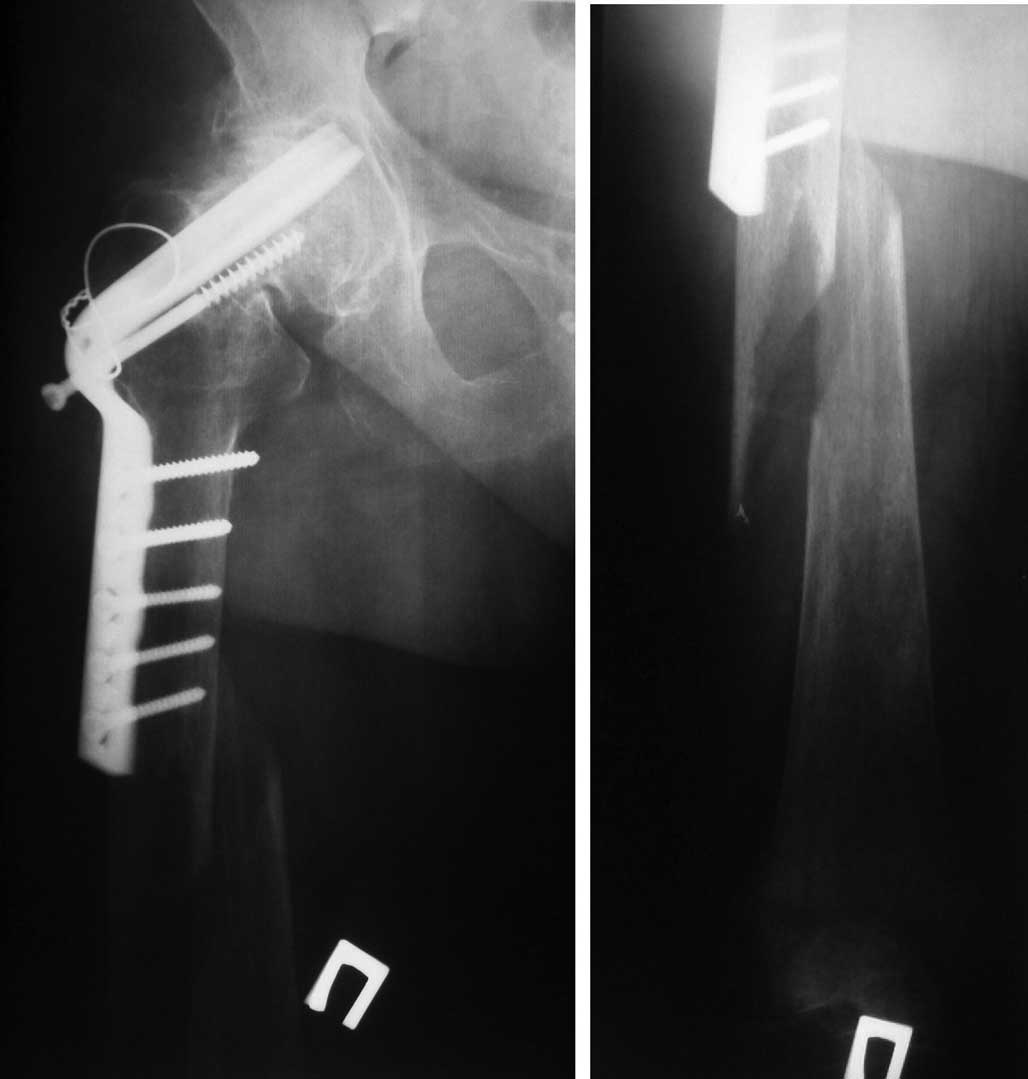

Женщина 86 лет, 7 лет назад корригирующая остеотомия по Mc Murray по поводу ложного сустава шейки бедра. Двигательная активность в пределах квартиры, передвигалась с дополнительной опорой и обслуживала себя, все это время к врачу не обращалась.

Упала по неосторожности, доставлена СМП. Проводится склетное вытяжение. Планируем - имеющийся фиксатор не трогать, т.к. он участвовал в опорности этой конечности (7 лет пациентку устраивал) и у нас нет полной уверенности в сращении ложного сустава.

Учитывая проблемный соматический статус : тучность , ХОБЛ; оперативное вмешательство планируем с минимальной агрессией, не вмешиваясь на винтообразный прелом, растянуть на дистракционной приставке по методике LIIS, накостная фиксация LSP 5.0 мм, располагая фиксатор по передне-боковой поверхности бедра.С удовольствием выслушаем советы по лечению этого перелома.

Не потому ли пациентка передвигалась с дополнительной опорой, что клинок в вертлужной впадине?

Уважемые колеги,на мой взгляд пластину стоит удалить (пенетрация клинка в сустав, вылезший компрессирующий винт, резорбция вокруг клинка).

В данном случае, с моей точки зрения, для выбора дальнейшей тактики лечения чрезвычайно важно установить факт сращения перелома шейки бедренной кости. Можно было бы получить дополнительную информацию о степени сращения, выполнив РКТ тазобедренного сустава. Если сращение перелома шейки бедренной кости не достигнуто, то наиболее приемлемой, мне представляется, будет тактика, предложенная авторами. Однако, фиксация пластинкой перелома порозной кости у лица восьмидесяти шестилетнего возраста оставляет пациента прикованным к постели до сращения перелома, хотя и с неочевидной перспективой передвижения после сращения. Иное дело, если установлен факт сращения перелома шейки бедренной кости. В этом случае имеется возможность обеспечить возможность больной нагружать ногу сразу после оперативного лечения. Тяжесть оперативного лечения в данном случае, мне кажется, будет зависеть не столько от величины разреза на бедре, сколько от времени оперативного вмешательства. Не являюсь сторонником ретроградного остеосинтеза у лиц пожилого возраста, из-за нескольких случаев, подобных приведенному на вложенном файле.

из-за нескольких случаев, подобных приведенному на вложенном файле

Чтобы не сталкиваться с такой проблемой, оптимально стержень запирать не латеро-медиально, а передне-задними винтами (достаточно одного). И стержень желательно ввести проксимальнее малого вертела.